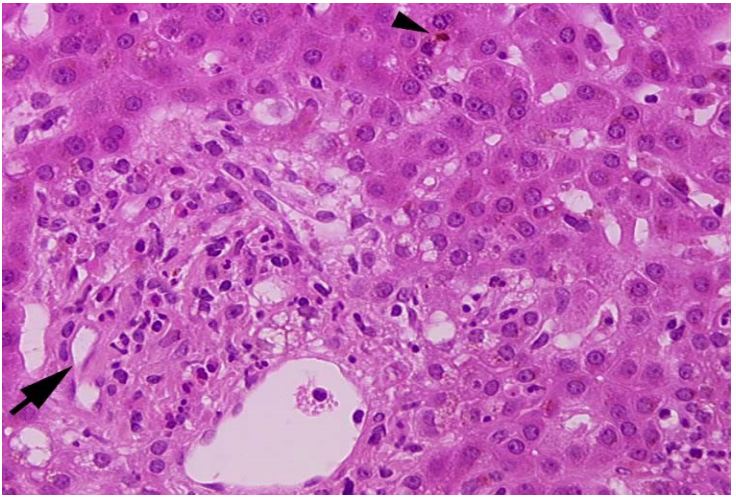

Figure 3 & 4: 4 months later, centrilobular cholestasis was major (arrow head) and the loss of bile duct was definite, confirmed by CK7- immunostaining which showed no duct inside the portal tract and a clear periportal biliary metaplasia (severe ductopenia).